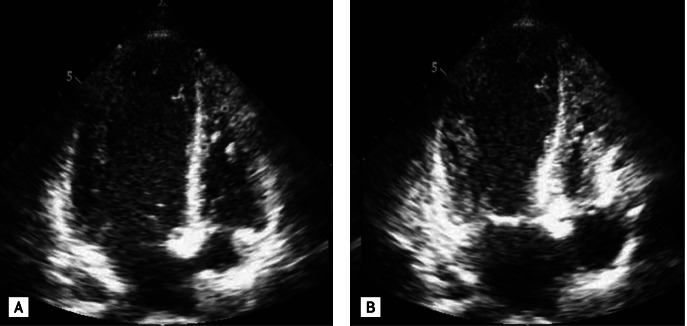

Figure 2

Apical four-chamber transthoracic echocardiography view during (A) diastole and (B) systole showing apical ballooning of the left ventricle due to akinesis from the apical to midventricular segments, and hyperkinesis of the basal segments with a markedly reduced left ventricular ejection fraction of 28%.

A 21-year-old female presented to the emergency room with disturbed consciousness and a seizure. She had no relevant medical history. She had been taking dietary supplements purchased via the internet for the proceeding week in order to lose weight. The supplements contained caffeine and synephrine. The physical examination revealed a blood pressure of 115/84 mmHg and pulse of 110 beats per minute. On auscultation, the lungs were clear and heart sounds normal, with no murmur or gallop. The 12-lead electrocardiograph revealed sinus tachycardia, T wave inversion in leads II, III, aVF, and V3-6, and a prolonged QTc interval of 537 ms (Fig. 1). Laboratory analysis revealed creatine kinase (CK) 374 U/L (normal range, 21 to 215), CK-MB 9.9 ng/mL (normal range, < 4.3), troponin I 0.59 ng/mL (normal range, < 0.07), brain natriuretic peptide 734 pg/mL (normal range, < 100), and C-reactive protein 3.6 mg/L (normal range, 0.1 to 6.0). The serum catecholamine levels measured 3 days after admission showed dopamine 6.03 ng/mL (normal range, 0.5 to 6.2), epinephrine 0.03 ng/mL (normal range, < 0.3), and norepinephrine 0.48 ng/mL (normal range, < 0.8). Transthoracic echocardiography (TTE) performed at the day of admission showed apical ballooning of the left ventricle due to akinesis from the apical to midventricular segments, and hyperkinesis of the basal segments, with a markedly reduced left ventricular ejection fraction of 28% (Fig. 2). The impairment extended across the coronary artery distribution. Cardiac magnetic resonance (CMR) was performed 2 days after admission. The cine CMR findings were consistent with TTE (Fig. 3A and 3B) and the late enhancement CMR revealed no late gadolinium enhancement (Fig. 3C). In addition, reconstructed CMR images of the coronary arteries revealed no significant stenosis (Fig. 3D and 3E). Under a working diagnosis of ABS, she was treated conservatively with a β-blocker, angiotensin converting enzyme inhibitor, and loop diuretics. Gradually, her symptoms improved. Another TTE performed 9 days after admission revealed a normal ejection fraction of 63%, with complete recovery of the apical and midventricular wall motion. While hospitalized, neurological evaluations including electroencephalography and brain magnetic resonance imaging were performed to determine whether epilepsy was the cause of her seizure. However, there was no definite evidence of epilepsy or other organic brain abnormalities. Therefore, she was not given any antiepileptic medication. She remained stable clinically and hemodynamically for 10 days of hospitalization and was discharged home without cardiological or neurological sequelae. In the year since, there has been no recurrence of ABS or seizures.